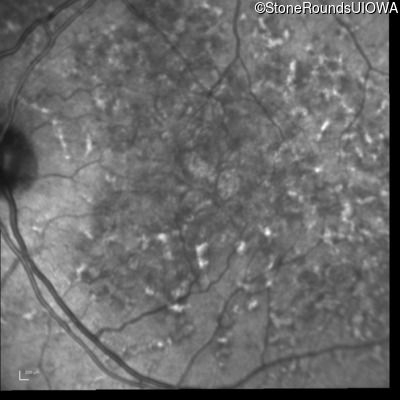

Blue Autofluorescence - Left - 20/32 sc

Exemplar